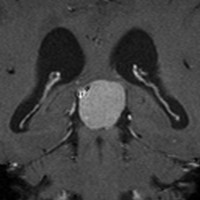

大後頭孔(大孔)髄膜腫 foramen magnum meningioma)

この腫瘍はfarlateral approachなどの頭蓋底手術をしなくても,外側後頭窩開頭で全摘出できます。要領は,S状静脈洞の下端の周囲骨を削除することです。大後頭孔髄膜種は延髄を圧迫するので巨大なものはありません。出血のコントロールや延髄からの剥離は比較的容易なものが多いでしょう。舌咽神経と迷走神経損傷を避けることが重点となります。

迷走神経と舌咽神経は機能温存できました。舌下神経が腫瘍の表面に薄く広がり剥がすことができずに半分以上を切断しています。でも片側舌下神経麻痺では日常生活に困ることはあまりありません。